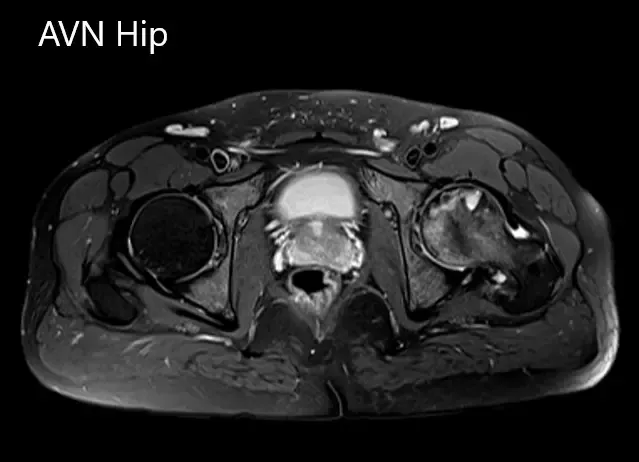

Se realizó una resonancia magnética que sugirió necrosis avascular de la cadera izquierda, estadio 3. Hubo una intensidad alterada de la señal y edema de médula ósea.

Secciones axiales de la T1WI y T2WI de la RM.